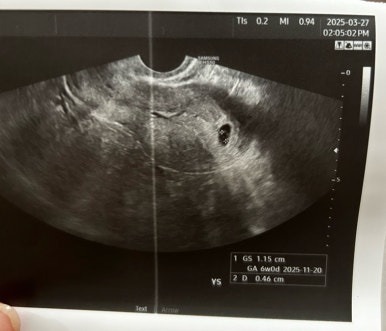

(3/20 아기집 , 3/27 난황)

아기집은 1.15cm로 커졌고

그 안에 0.46cm의 난황이 생겼다 !!!